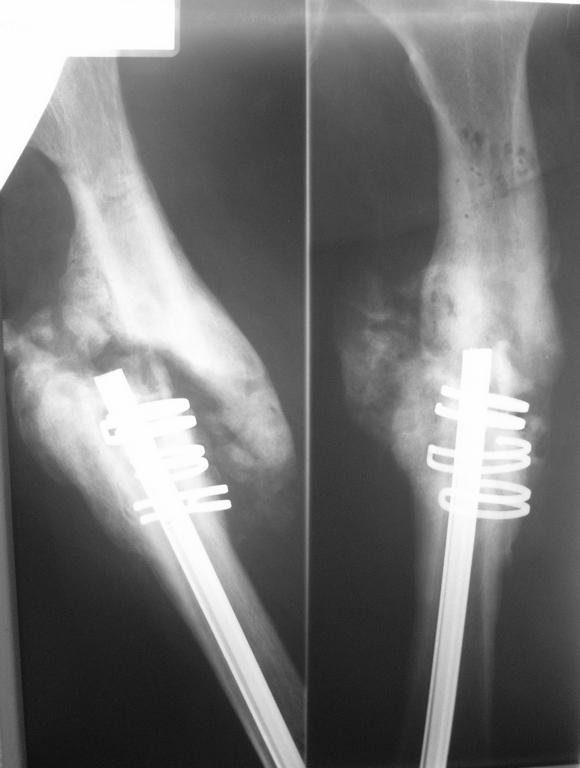

В декабре 2006г политравма в результате ДТП,соп.дз: Закрытый винтообразный оскольчатый перелом с/з правого бедра. Выполнена открытая репозиция, остеосинтез гвоздем Кюнчера + кольца NiTi. Через 15мес штифт сломался, был наложен АВФ, осложнением которого явился остеомиелит бедренной кости.